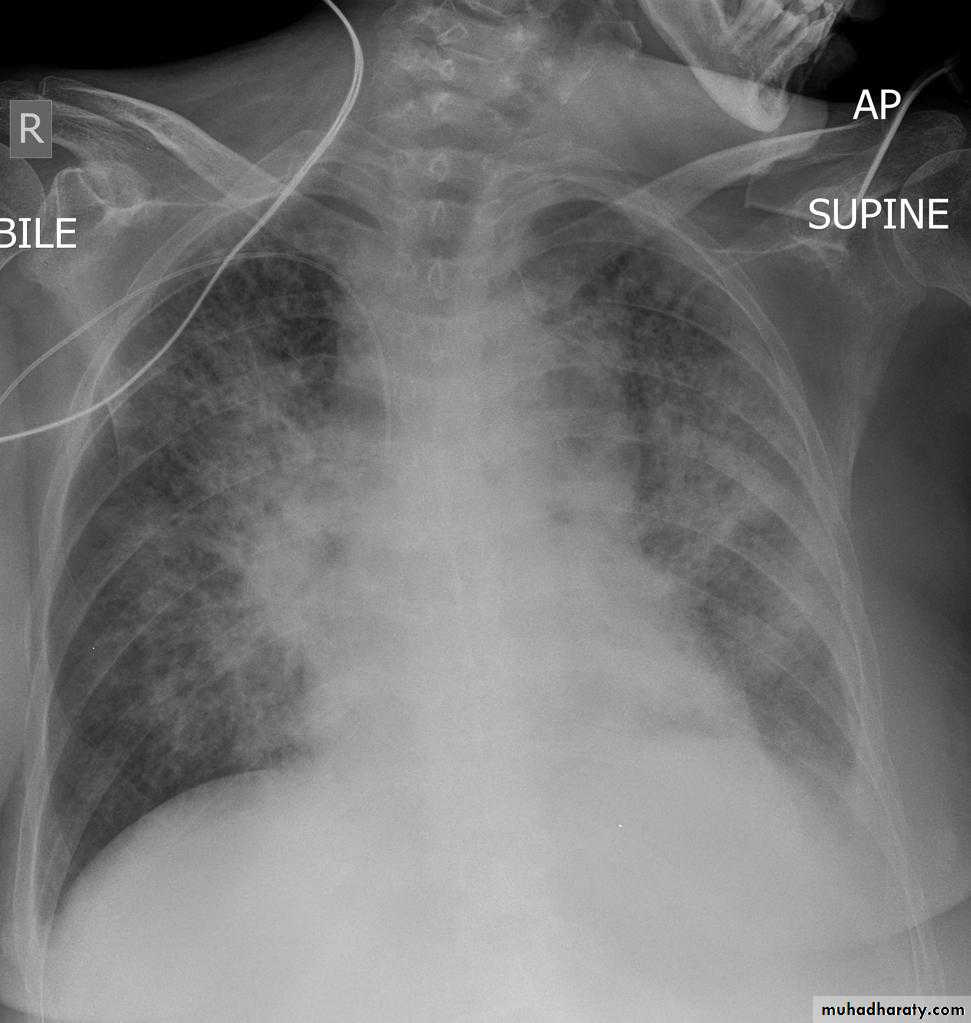

Pulmonary edema ( alveolar pulmonary edema)

Bat wing sign ( alveolar pulmonary edema)

38.interstial pulmonary edema

39.pulmonary edema ( alveolar pulmonary edema )

40.batwing sign ( alveolar pulmonary edema )